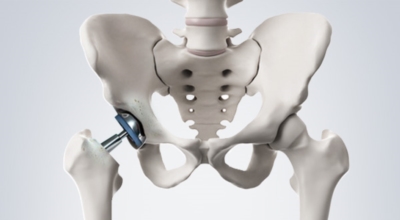

고관절 통증 치료에는 크게 약물 치료와 물리 치료가 있어요. 고관절염의 진행을 늦추거나 증상을 개선하기 위한 목적으로 항염증제 또는 진통제를 투여합니다. 고관절 질환의 일부 증상은 체외 충격파, 물리치료, 약물치료 과 같은 비수술 요법으로 증상이 호전될 수 있답니다.

그러나 비수술 치료법으로 개선시키는 것이 어려운 경우 수술적 방법이 고려됩니다. 고관절 통증을 조기에 치료하면 약물치료 외에 물리치료로 약 50% 정도 큰 효과를 볼 수 있어요. 게다가, 보통 고관절 증상 관리에 도움되는 요가, 수영, 스트레칭은 고관절 예방과 치료에 도움 됩니다.